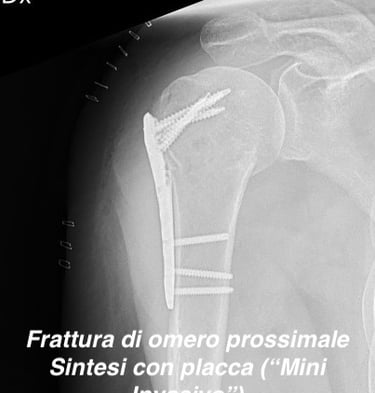

Patologia traumatica di spalla (scapola, clavicola e omero)

Gallery

Attività Chirurgica